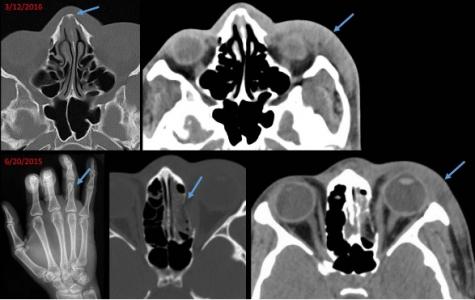

Car l’imagerie peut également apporter des indices précoces d'abus, de violence ou d’agression sexuelle. Un cas en particulier a motivé cette équipe du Brigham and Women's Hospital, une jeune femme de 21 ans présentant une fracture chronique des os du nez et un gonflement des tissus mous du visage latéral gauche ainsi que les séquelles d’une fracture guérie. En retrouvant les images médicales précédentes de cette patiente dans le système d'archivage de l'hôpital, le radiologue a retrouvé une fracture récente du poignet. Cette succession de blessures a permis aux radiologues de suspecter un cas de violence conjugale, qui avait, dans ce cas, échappé au médecin. L’équipe a ensuite poursuivi ses recherches pour tenter de caractériser les résultats cliniques et radiologiques chez les victimes de violence conjugales et/ou d’agressions sexuelles.

Des blessures caractéristiques : les chercheurs ont donc examiné les dossiers médicaux électroniques des patient(e)s orienté(e)s vers les programmes de soutien dédiés aux victimes de violence conjugale et d'agression sexuelle et pu ainsi identifier les blessures caractéristiques chez les patients. Sur le plan radiologique, les auteurs définissent ainsi « des modèles communs de blessures » dont des lésions des tissus mous, les fractures des membres fréquemment localisées aux extrémités supérieures distales et suggérant des blessures liées à des tentatives défensives. Les fractures faciales, qui représentent une zone cible de traumatismes sont également fréquemment observées. Bref, toutes ces blessures caractéristiques doivent alerter les radiologues de l’éventualité de violences commises par le partenaire intime. Précisément,